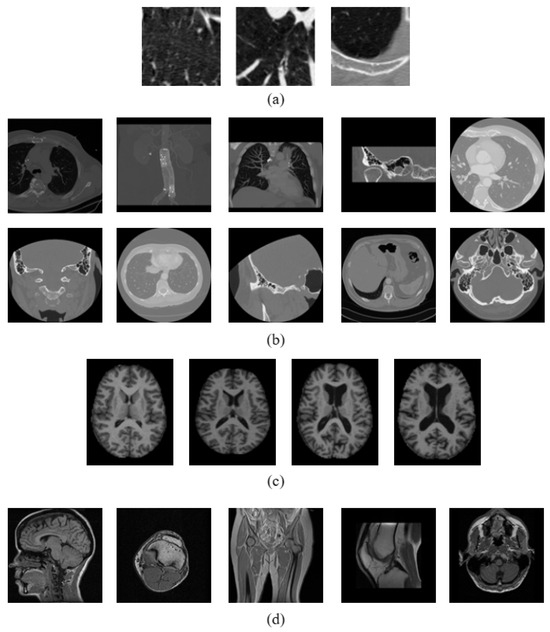

3.3. Dataset Description

| CT Image Datasets | MR Image Datasets | |||

|---|---|---|---|---|

| Emphysema CT | NEMA CT | OASIS MRI | NEMA MRI | |

| No. of Images | 168 | 600 | 416 | 372 |

| Image Size | 61 × 61 | 512 × 512 | 208 × 208 | 256 × 256 |

| No. of Classes | 3 | 10 | 4 | 5 |

| Images per Class | 59, 50, 59 | 54, 70, 66, 50, 15 | 125, 104, 91, 96 | 72, 100, 76, 59, 65 |

| 60, 52, 104, 60, 69 | ||||